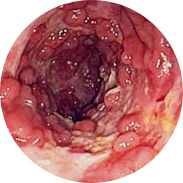

Vnetje in suppuracija rektalne sluznice

Krvavitev lahko vodi do razvoja anemije

Povišanje telesne temperature pri hudem vnetju lahko povzroči

mrzlico

In najhuje je rak danke!Obsežna klinična študija Hemorena je bila izvedena v Kliničnem centru (Ljubljana) leta 2016. Skupaj je v študiji sodelovalo več kot 1000 moških in žensk z različnimi stopnjami hemoroidov. Vsi preiskovanci so 3 tedne uporabljali kremo Hemoren. Rezultati študije so osupnili celo zdravnike!